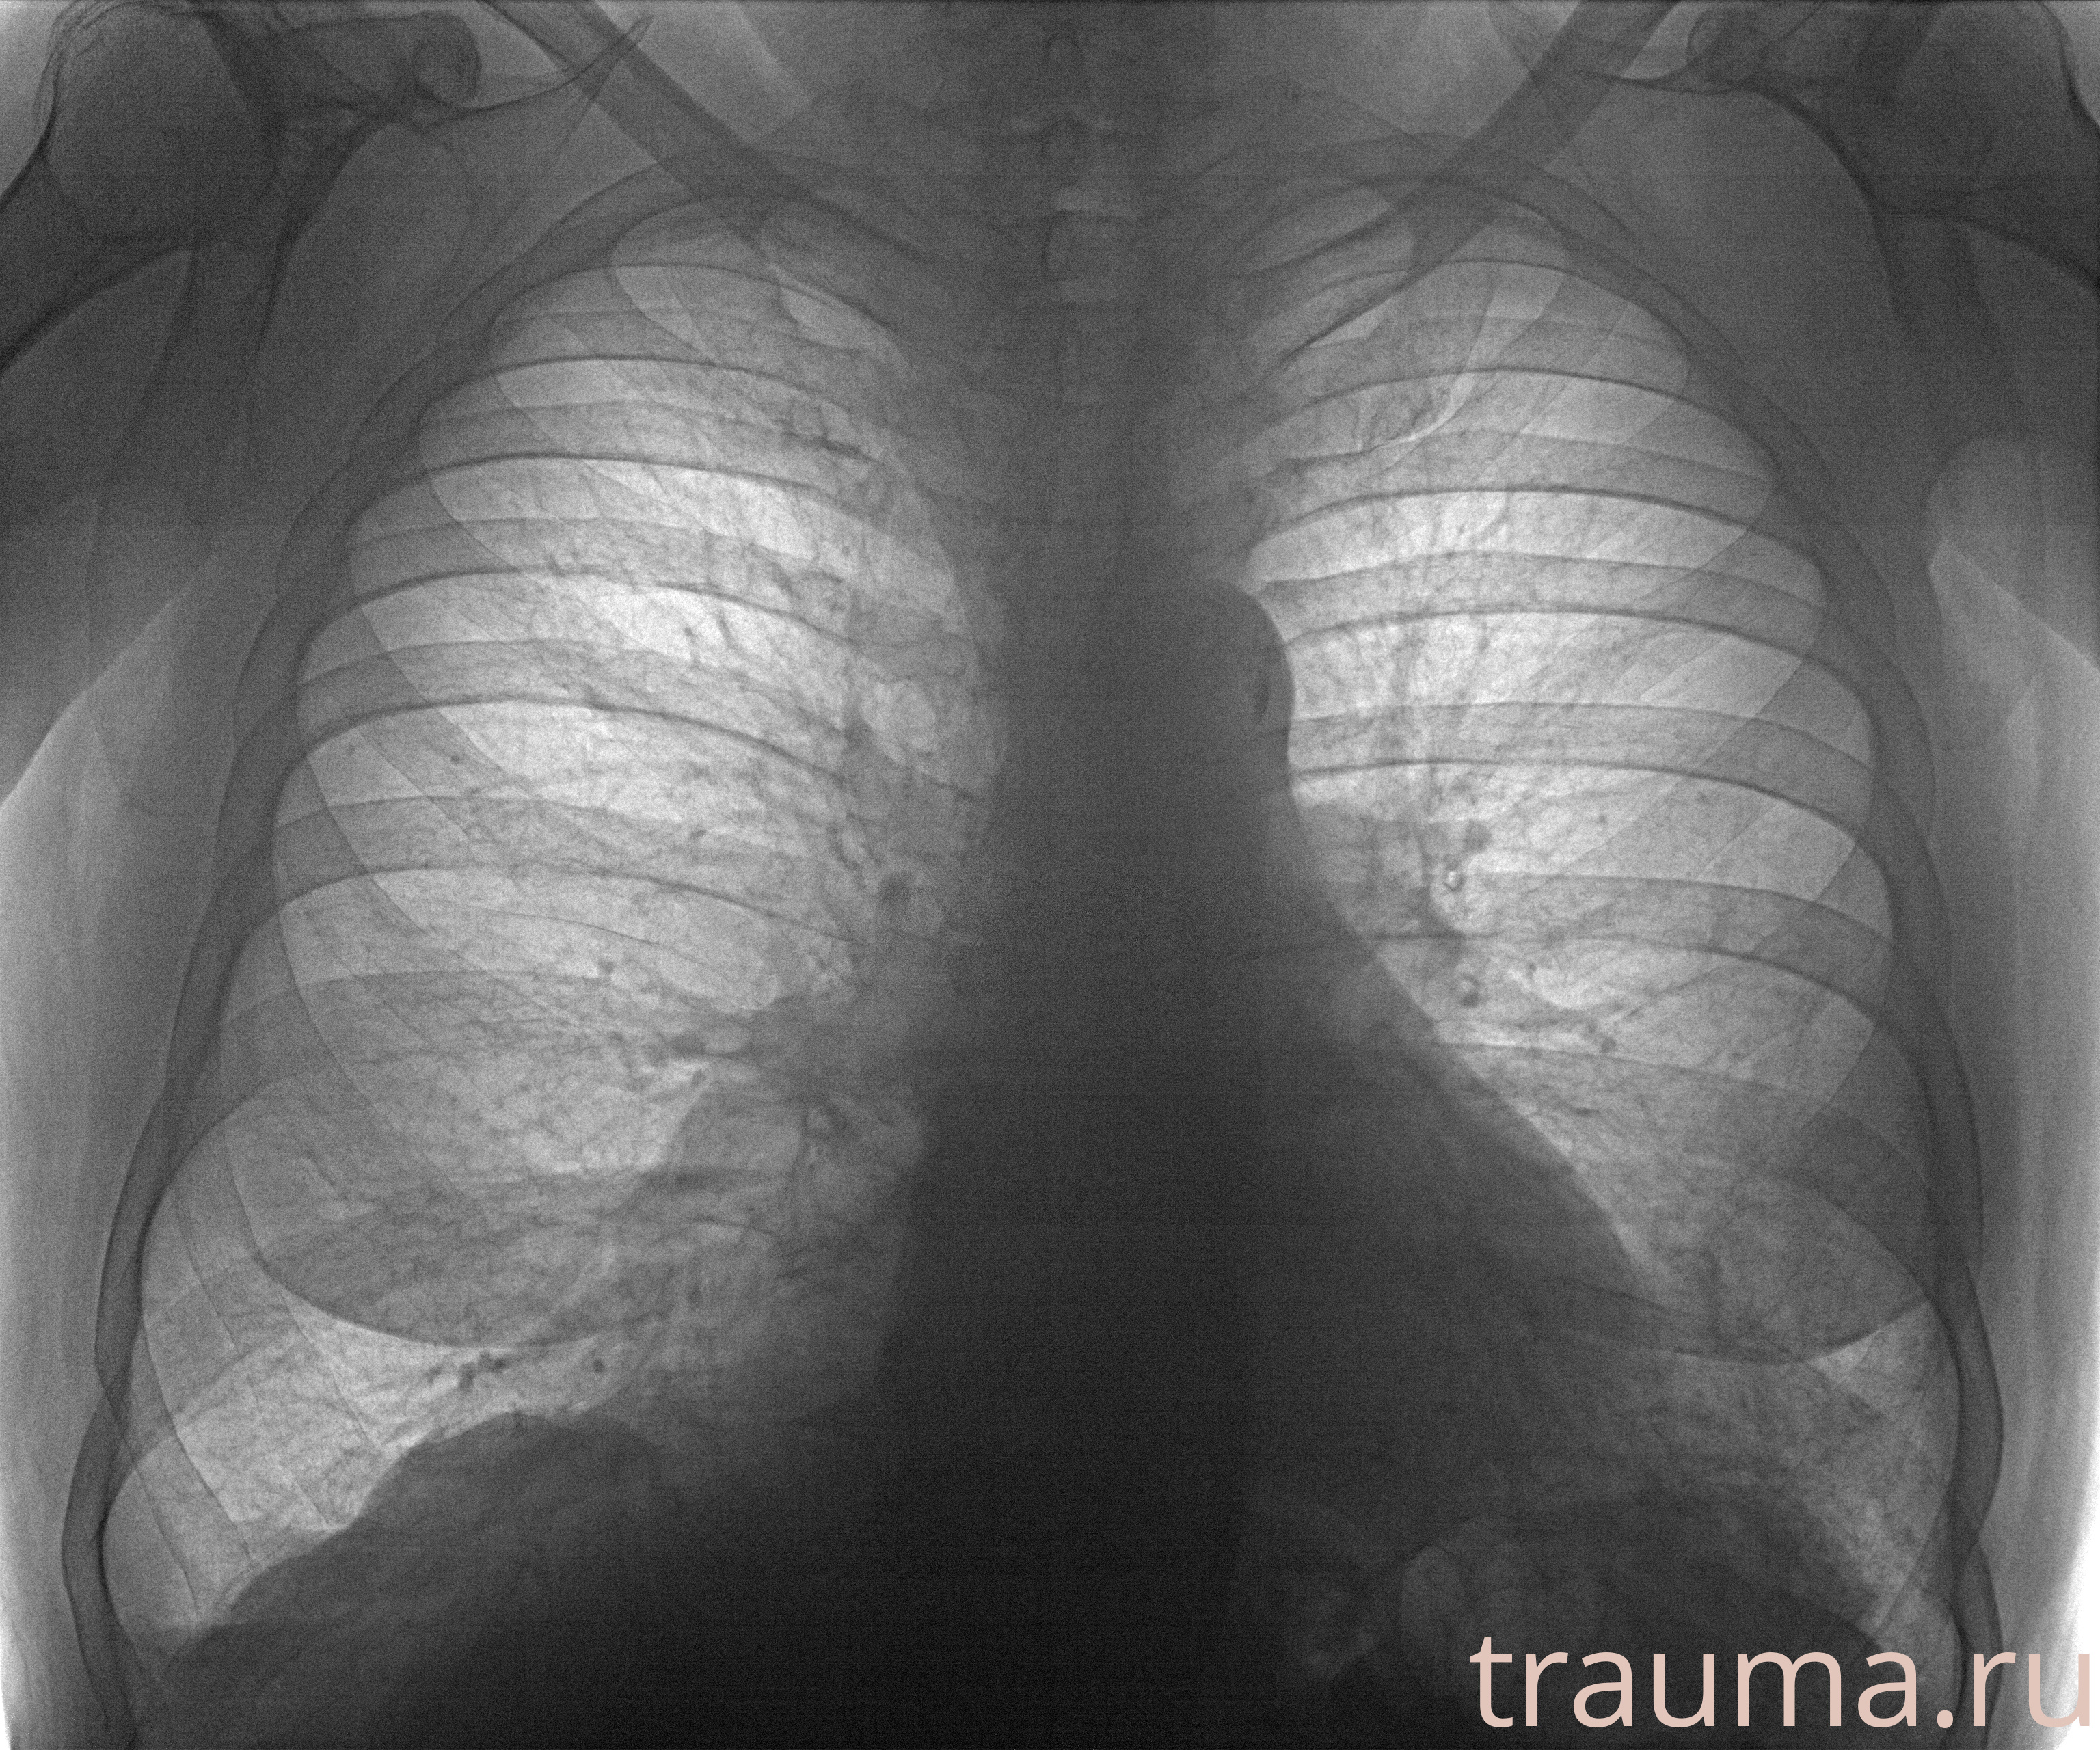

Рентген на дому: по вашему адресу приезжает врач-рентгенолог, травматолог-ортопед с мобильным рентгеновским аппаратом, проводит диагностику травмы или заболевания, делает необходимые рентгенограммы, дает рекомендации по дальнейшему лечению. Получить качественные снимки в домашних условиях возможно благодаря уникальной методике, разработанной МосРентген Центром для института  Склифосовского